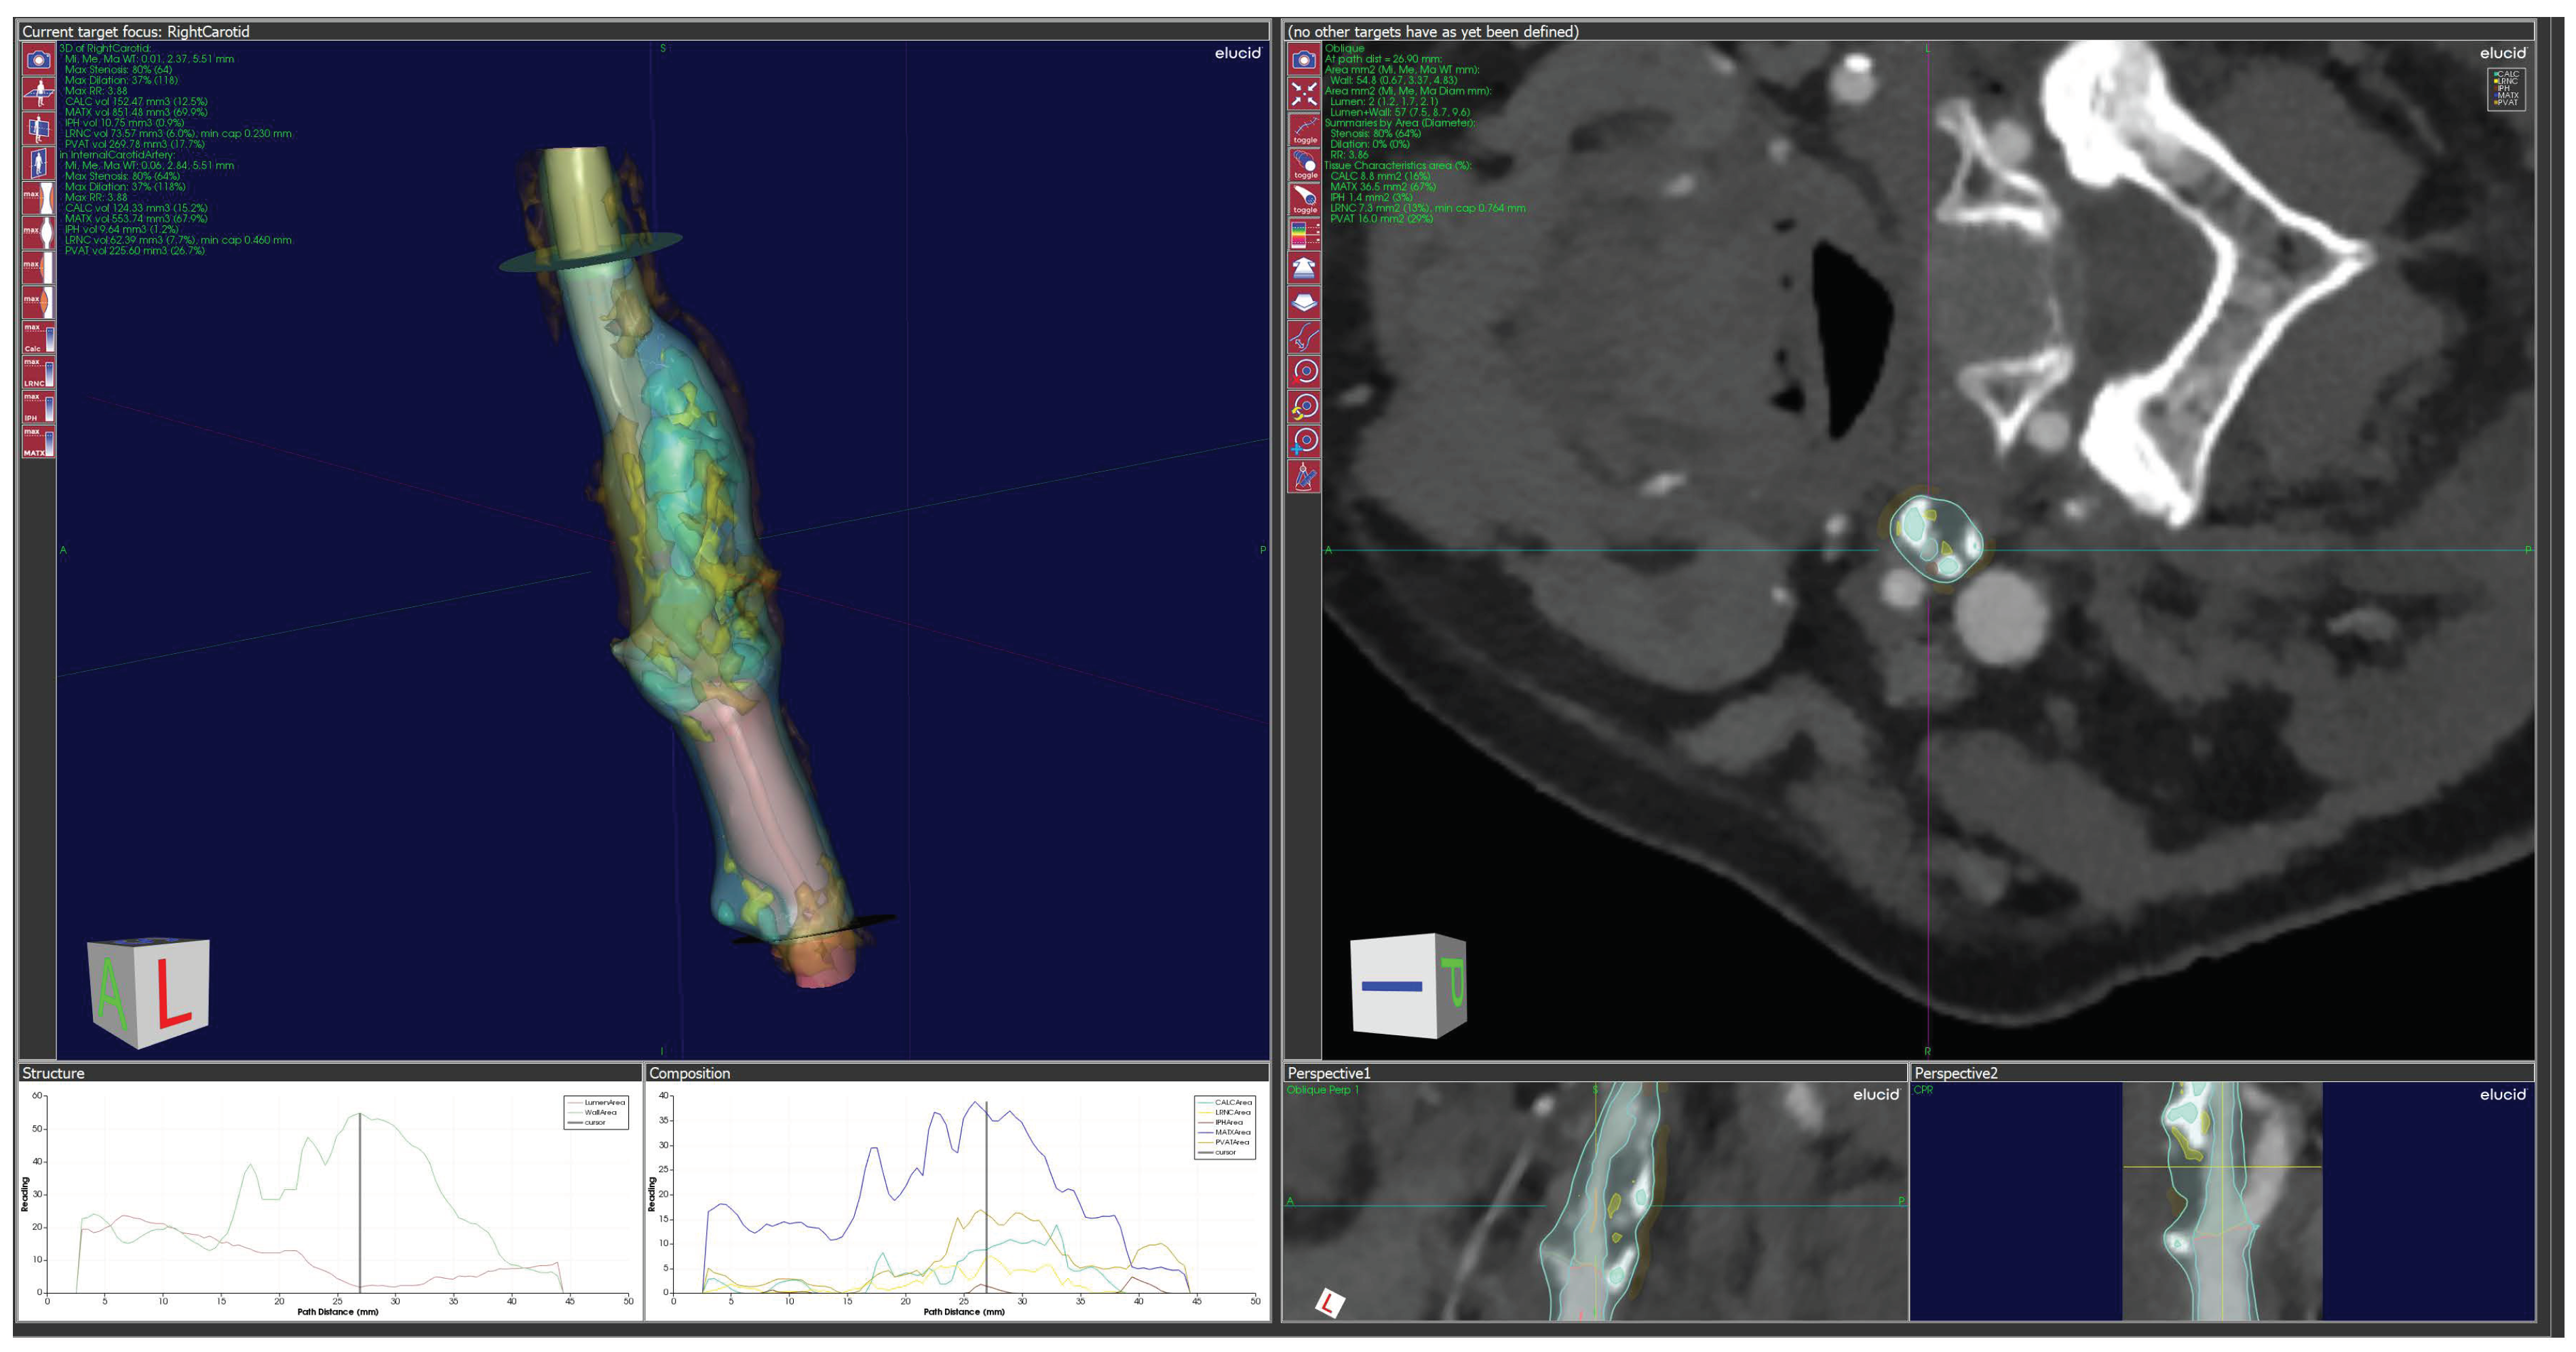

Quantitative Plaque Analysis